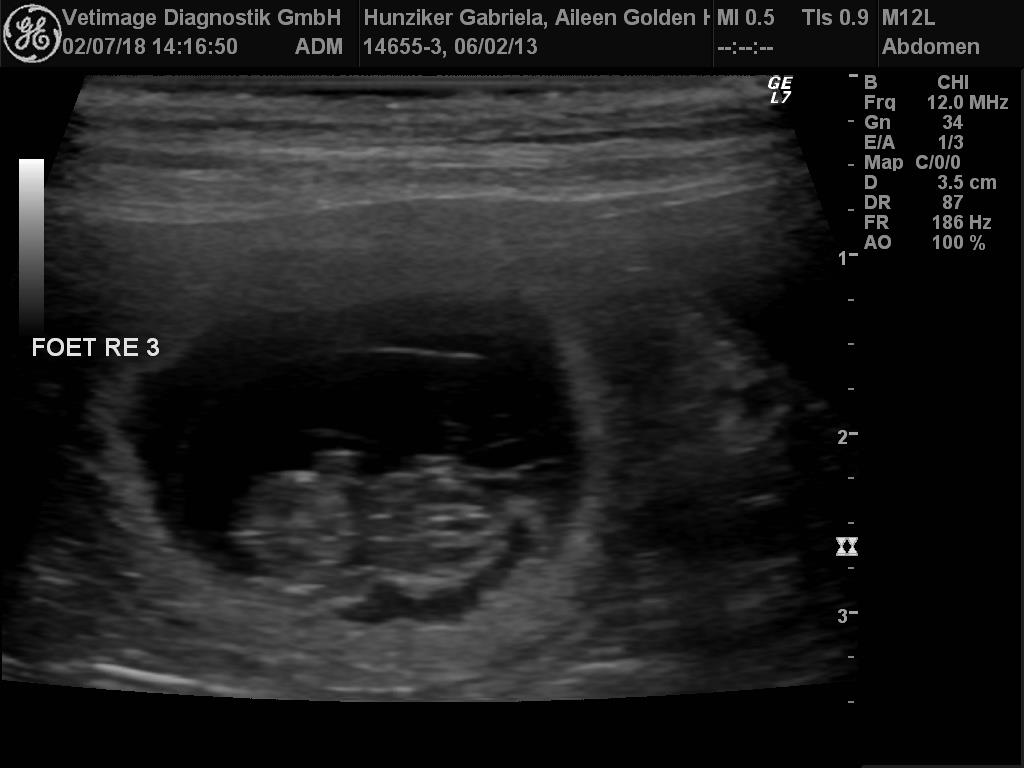

F-Wurf Ultraschall

Wiederum dürfen wir uns freuen... unsere Aileen und Camillo de Manescale werden Eltern.

Diese Verpaarung hat einen speziellen Stellenwert für uns und wir sind sehr gespannt und freuen uns auf die kommenden Wochen.